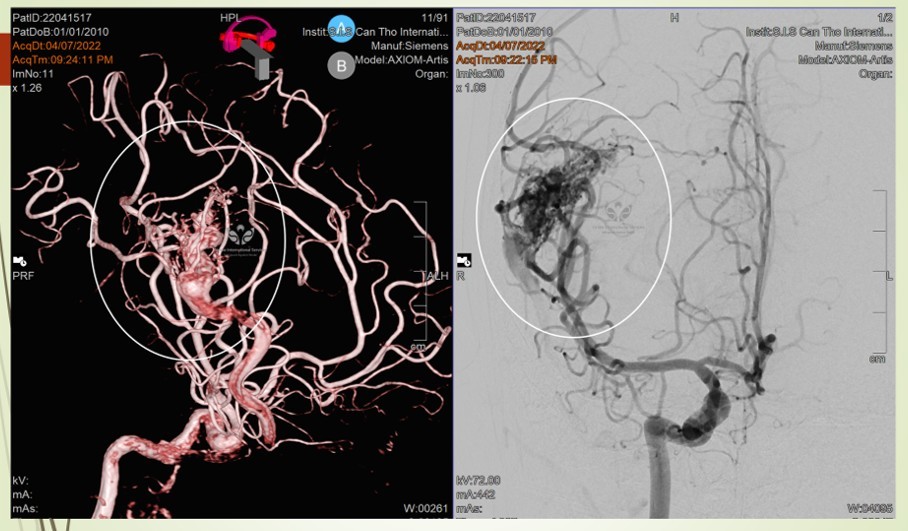

Thông tin trên Tổ Quốc, bệnh nhi vào cấp cứu tối 7/4 với biểu hiện đau đầu dữ dội kèm theo nôn ói. Khi vào viện bác sĩ đã nghi ngờ xuất huyết não do vỡ phình mạch máu não.

Khi xảy ra đột quỵ ở trẻ em, thì ngày nay sẽ điều trị theo phương pháp can thiệp nội mạch DSA, ít xâm lấn, đặc biệt là điều trị được những vùng não sâu mà phẫu thuật không mổ tới. Ngoài ra, sau can thiệp trẻ nhỏ bảo tồn được phần lớn chức năng, không để lại bất kỳ vết sẹo nào.

Di dạng mạch máu não là bệnh nguy hiểm nhưng nếu được chẩn đoán sớm có thể điều trị khỏi hoàn toàn. Hiện nay, phương pháp chụp mạch máu não bằng ứng dụng DSA giúp bác sĩ có cái nhìn chính xác về vị trí, kích thước, hình dạng của đoạn mạch dị dạng đồng thời vẽ được biểu đồ huyết mạch nơi mạch máu dị dạng phát sinh.